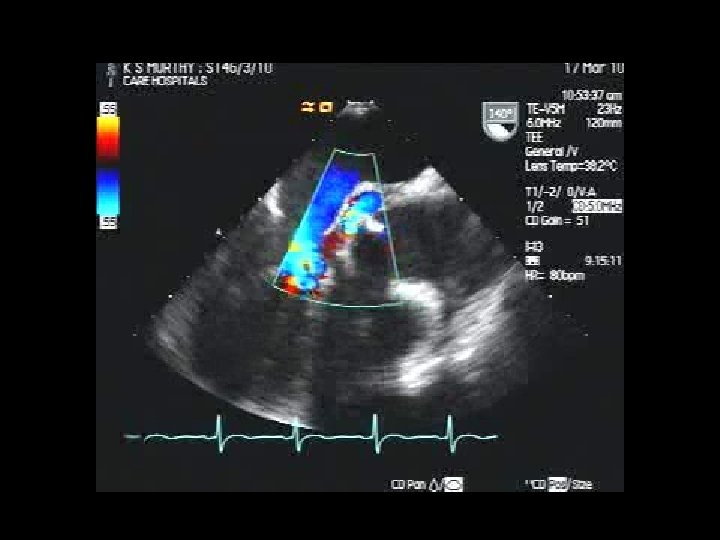

Anjali Bhattacharya MVR ( Tilting disc) Pro Valve dysfunction Pre and Post Lytic (Rx)